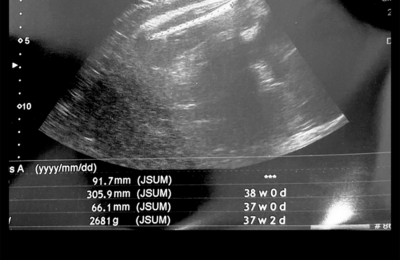

2週間ぶりに検診行ってきました! 妊娠期間なにかにつけて切迫気味の私ですが、なんとか子宮頸管長は35mmとセーフでした! 赤ちゃんの大きさは週数相当☺️ ただ測ってる時になんかいつもより内側を測りがちだなーとかお腹の大きさはすごい斜めに測るなーと思ったので、実際はもう少し大きいような気もします😇 私は車の関係で月曜か金曜に検診に行くのですが、月曜の先生と金曜の先生で厳しさが全然違う✋😊 月曜の先生…